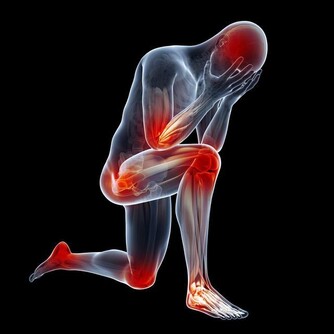

腿腳抽筋可能是因為過度疲勞:

隨著人們生活物質的提高,但是對於相當一大部分的人群來說,身上的重擔也不少,

尤其是對於中老年人來說,長期處於一種體弱疲勞的狀態,

再加上自己在運動方面過於嚴格的規定,導致運動過度,讓機體產生了大量的代謝廢物。

到了晚上的時候還沒有緩解掉,那麼就容易引起腿腳抽筋的現象,

一般情況下,可持續的時間在十秒或者是數秒以上,影響我們正常的睡眠。